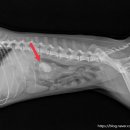

• 선부중앙동물의료센터 | 안산 고양이 이물 수술 전문 | 선부중앙동물의료센터 소화기 수술 후기 및 입원 관리

안녕하세요, 안산의 모든 반려가족분들! 선부중앙동물의료센터입니다. 🐾 고양이를 키우는 집사님들이라면 한 번쯤 '혹시 우리 아이가 이걸 먹은 건 아닐까?' 하는 걱정에 가슴이 철렁했던 적 있으실 거예요. 고양이는 호기심이 많고 혀의 돌기 때문에 이물질을 삼키기 쉬운 구조를 가지고 있거든요. 오늘은 소화기 이물...